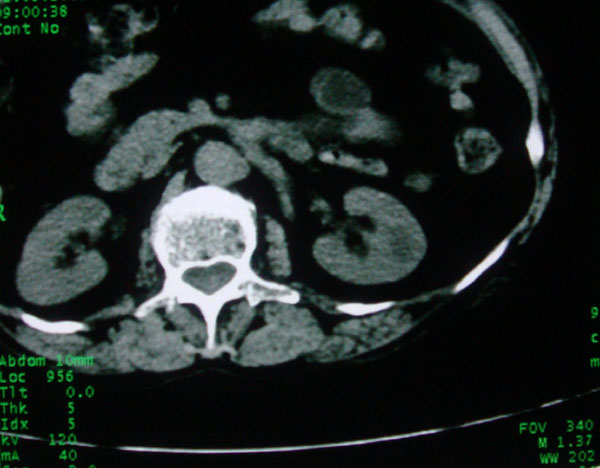

患者女性体查.发现左肾有低密度影,大家考虑是什么.其它方面没有什么异常.低密度影ct值约22hu.

左肾低密度影,境界尚清,查体发现,临床无其他首先考虑肾囊肿,如果增强一下对鉴别有帮助。

左肾不均匀低密度,其形态不规则、边界不清楚,更谈不上锐利。虽无局部凸出,但最后一张片显示仍有比较明显的隆起,我多考虑为肾癌,建议增强或mri检查。